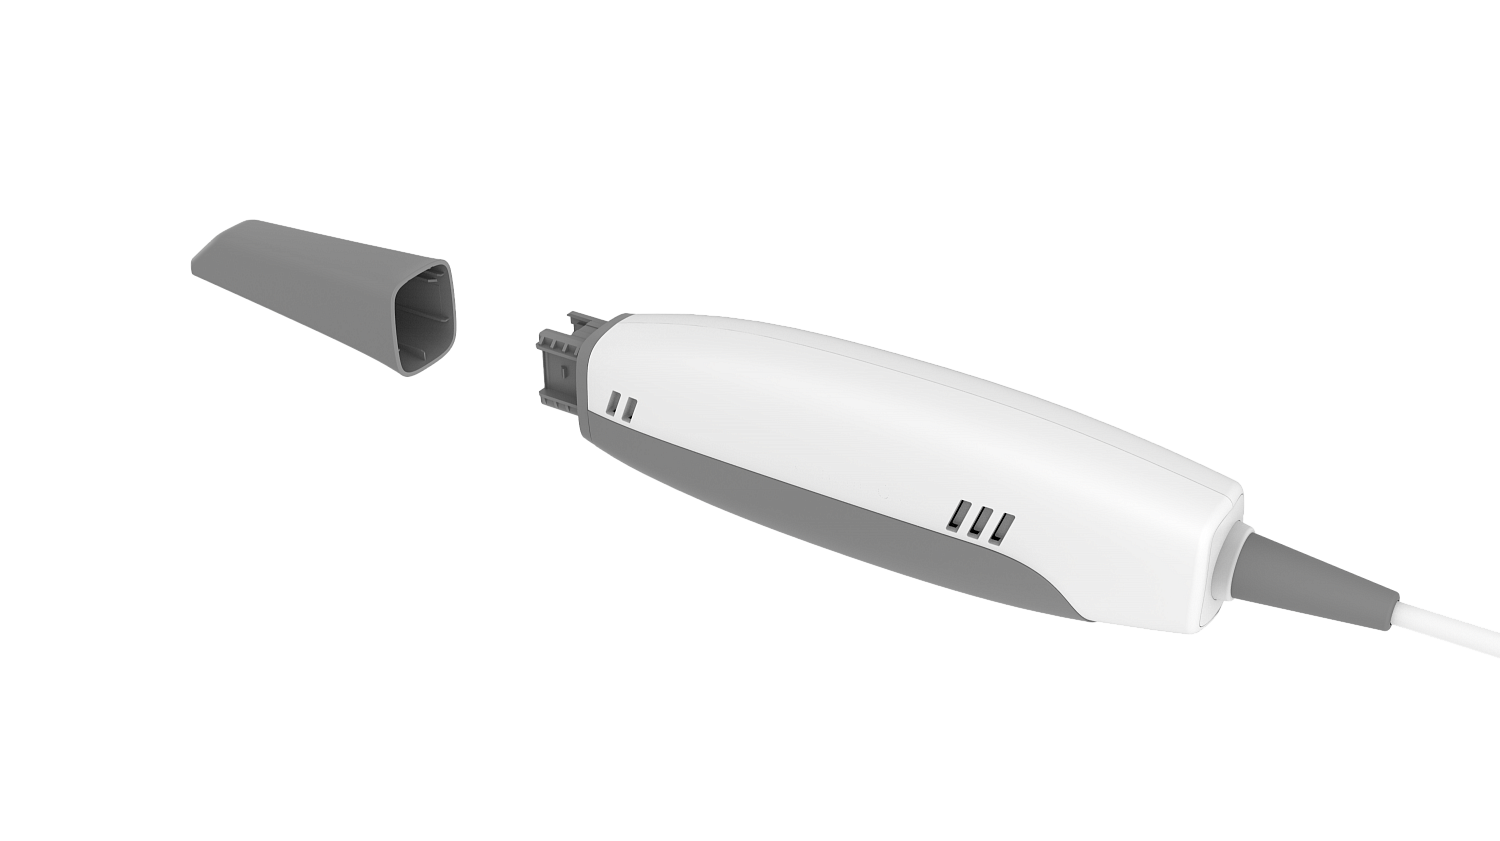

- digital scanner

With experience and careful planning the clinician becomes more confident of delivering great clinical outcomes consistently. Having just the first two components, the digital scanner and the software, would already give the clinician the advantage of control over the case compared to using a third party provider.